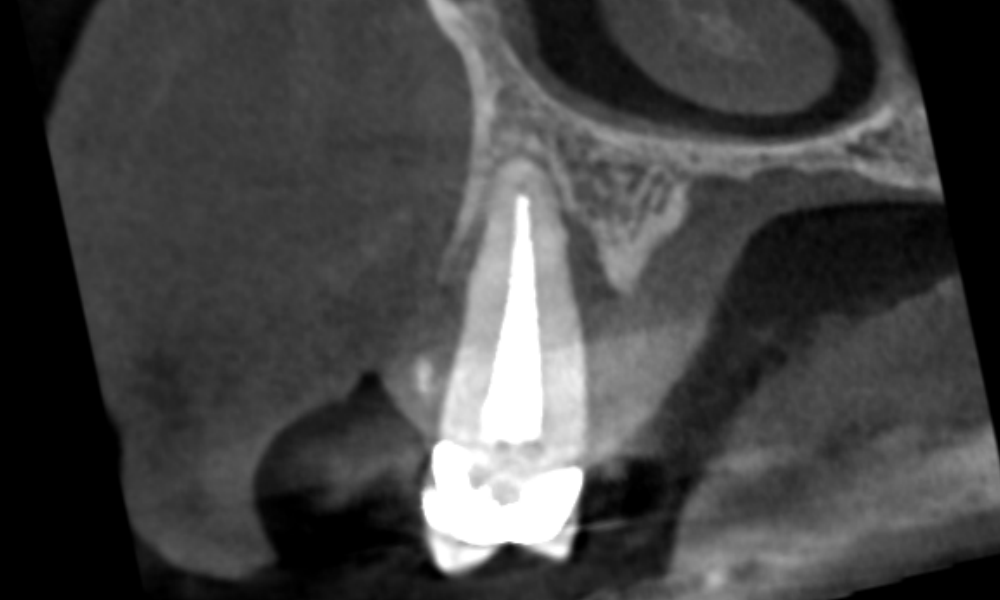

Case 24 – Endodontics

Transillumination after trauma